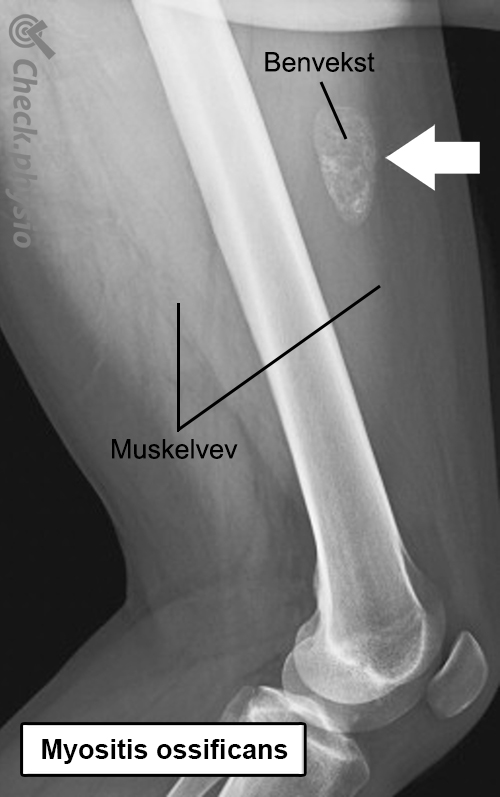

Myositis ossificans Beindannelse i en muskel

Når det dannes bein i en muskel, kalles det myositis ossificans. Dette er som regel et resultat av en muskelskade der en blodutredelse omdannes til benvev. En stor blodutredelse etter en muskelskade fører til myositis ossificans i 10 til 20 % av tilfellene.

Myositis ossificans er en tilstand der en muskelskade fører til lokal dannelse av benvev i den aktuelle muskelen. Etter et (alvorlig) slag oppstår det en blodutredelse i muskelen. Kroppen reagerer ved å sette i gang en betennelsesreaksjon i muskelen (myositt). Det kan føre til varme, rødhet, smerte og hevelse. Denne reaksjonen bidrar til reparasjon og opprydning av blodutredelsen. Vanligvis skjer dette raskt og symptomene forsvinner i løpet av noen uker. Men ikke ved myositis ossificans. Her forkalkes blodutredelsen og et lite bein dannes. Dette kalles ossifikasjon.

Som regel leges en muskelskade raskt og ukomplisert. Ved myositis ossificans skjer imidlertid noe spesielt. Den oppståtte blodutredelsen omdannes gradvis til benvev. Prosessen starter ca. én uke etter skaden og er ferdig etter seks til sju uker. Årsaken til denne tilstanden er ukjent, og symptomene kan variere sterkt avhengig av plassering og størrelse på skaden.

Behandlende lege eller fysioterapeut vil stille spørsmål om problemet. Ved myositis ossificans oppstår symptomene som oftest etter en muskelskade som ikke bedres innen to uker. Ved klinisk undersøkelse er det en hard, smertefull kul i muskelen og nedsatt bevegelighet i leddet/leddene muskelen passerer. På et tidlig stadium viser ikke et røntgenbilde noen unormale funn, men etter tre til fire uker blir tilstanden synlig. En ultralyd kan oppdage tilstanden tidligere.